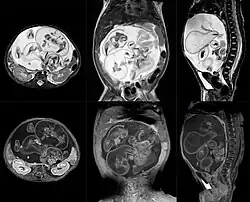

Ocurre en 1 de 1 000 000 nacimientos,[2][3] y se define como una masa fetiforme totalmente encerrada dentro del cuerpo del autósito o hermano desarrollado. Al extraerse, está envuelto en lo que parece un huevo de gallina, pero mucho más grande y extremadamente duro. El parásito, cuando es extraído y expuesto, tiene un color blanco. Una vez que se extrae, muere, ya que es un tejido totalmente dependiente de su hospedador. Al igual que en los gemelos parásitos, corazón y cerebro están ausentes o son muy rudimentarios. Puede estar más o menos organizado, con características muy variables, desde apenas una bola de tejidos hasta contener restos de pelo, hueso, manos con dedos y uñas y hasta piernas. La extirpación quirúrgica no presenta el menor problema dado que no pasan de ser tumores que pueden llegar a ser un potencial riesgo para su hospedador, debido a que se alimenta de este, representando para el hospedador una carga semiviva sin función en el organismo, y pueden llegar a malignizar.[4]